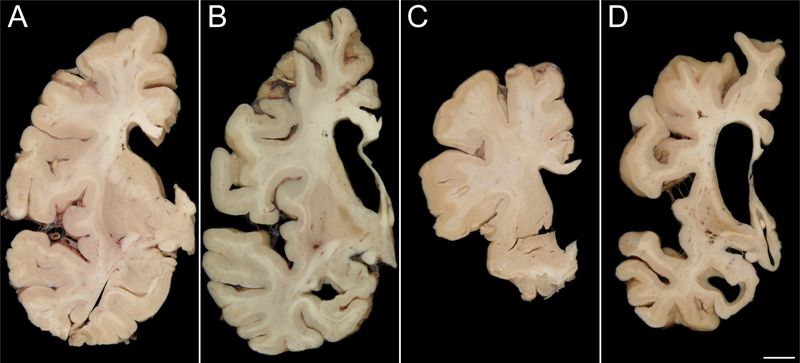

All 15 cases had evidence of frontal and temporal lobe atrophy, and hence all met criteria for FTLD. Striatal atrophy was observed in nine of the 15 cases (Table 2, Figure 1).

Figure 1: Striatal atrophy on gross examination

Striatal atrophy was not seen in many NIFID cases (A; Case 5) and was only observed in two cases (B; Case 6). Conversely, only one aFTLD-U case lacked marked striatal atrophy (C; Case 14) while the rest of the aFTLD-U cases demonstrated severe atrophy (D; Case 13) [bar: 1 cm].

Results of the light microscopic examination are shown in Table 2 and Figure 2. None of the 15 cases had evidence of tau deposition, and none met criteria for Alzheimer’s or Lewy body disease. All 15 cases were immune-reactive to ubiquitin. Thirteen of the 15 cases had neuronal inclusions that were immune-reactive to FUS. Seven of the 15 cases had eosinophilic inclusions that were seen on hematoxylin and eosin and were immunostained for α-internexin in keeping with their pathological diagnosis of NIFID. None of the remaining eight cases that had been diagnosed as aFTLD-U showed α-internexin immunoreactivity. Seven of the eight aFTLD-U cases (88%) showed severe striatal atrophy with FUS-positive neuronal cytoplasmic and vermiform intranuclear inclusions. Of the seven NIFID cases, five cases had neuronal inclusions that were immunoreactive to FUS. Unlike in aFTLD-U, striatal atrophy was only present in only 2/7 (29%) of the NIFID cases, both of which were FUS positive. Hence, neither of the two FUS negative NIFID cases had striatal atrophy. Therefore, 9/13 cases with FUS immunoreactive inclusions showed striatal atrophy while 0/2 without FUS showed striatal atrophy. Surprisingly, one of the two NIFID cases without FUS immunoreactivity had lesions that were immunoreactive for both α-internexin and TDP-43 (Figure 3).